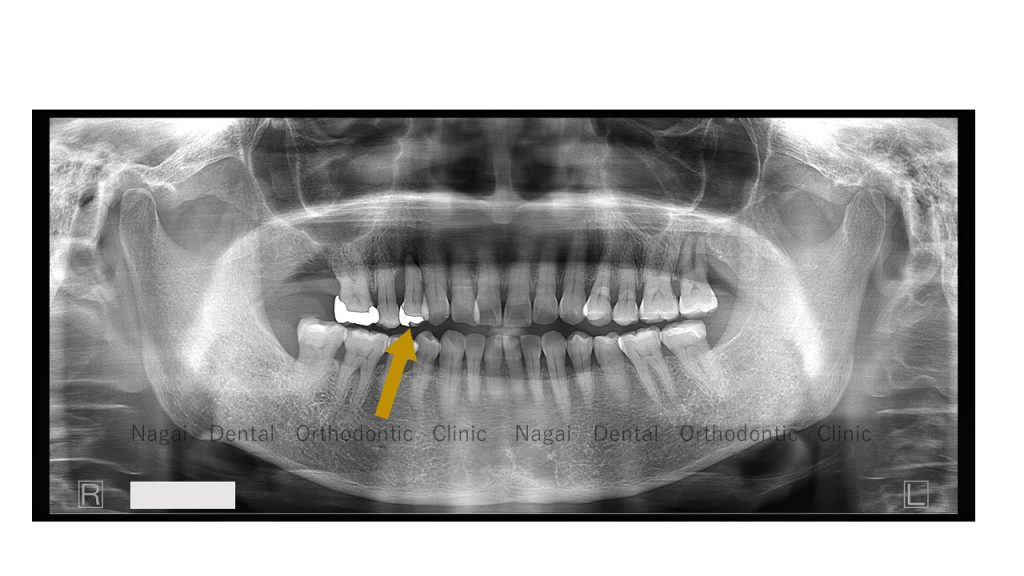

右上4番の歯が“プラプラ”と言う状態です。

●右上3番・4番・5番の噛み合わせを調整するため、ぐらぐらの4番を抜き3番から5番のブリッジ